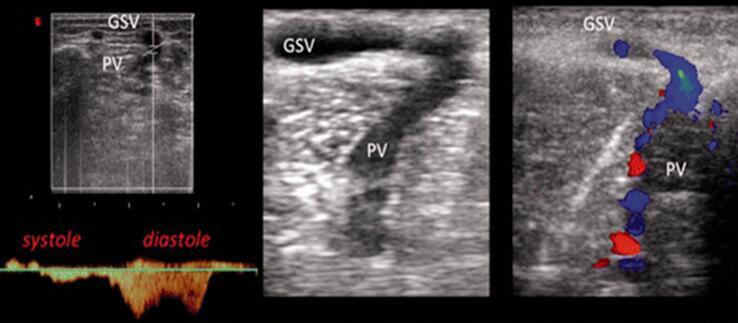

图20。返流的穿通支静脉:一个hunterian穿通支静脉(PV)功能不全,产生了深静脉系统向大隐静脉(GSV)的返流,既往通过结扎治疗。随之而来的能量梯度导致了复发,这一点通过PW和彩色多普勒分析得到了清晰的识别。

图21。生理性的穿通支静脉:是位于大隐静脉(GSV)主干上的穿通支静脉(PV)。务必要考虑网状血流的方向,而不只是流动时间。在此处报告的病例中,病房的舒张期血流明显很普遍,因此,单从流动时间看,它可以被认为是生理的,因为从更浅的静脉系统流动到深静脉系统。